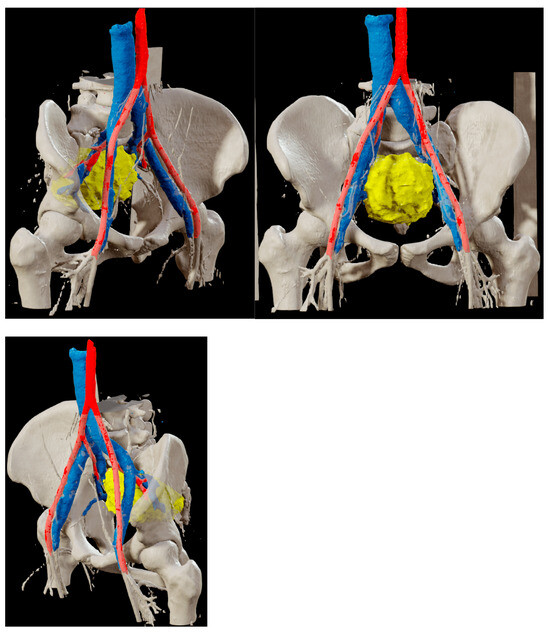

An Angio-CT scan was performed preoperatively (Figure 2) and used for 3D reconstruction of the vascular structures and their relationship with the lesion, utilizing Brainlab® (BrainLAB AG, Germany) planning software (Figure 3). Additionally, a 3D digital reconstruction of the pelvic mass, with a total volume of 240 cm3, was created from the contrast-enhanced MRI and fused with the Angio-CT data, allowing for precise 3D planning of the tumor’s position relative to surrounding vascular structures.

Figure 3. Digital 3D reconstruction of the presacral mass (yellow) and its relationship with the internal iliac vein (blue) and artery (red), based on Angio-CT scan data fused with contrast-enhanced MRI using Brainlab® planning software (BrainLAB AG, Germany). The reconstruction was utilized both preoperatively and intraoperatively to enhance the three-dimensional understanding of the lesion.